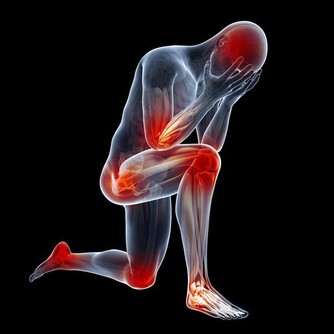

後來孩子說自己關節疼,喬女士認為生病了難免會覺得不舒服,自己感冒時也會覺得腰酸背痛的,於是安慰孩子沒關係,很快就會好的。直到她發現孩子身上莫名出現瘀青,牙齦還總是流血,她才意識到有點不正常。拿到報告單後她崩潰大哭,覺得是自己害了孩子,要不是自以為是拖這麼久,說不定孩子早就接受治療了。

醫生提醒:孩子貧血沒有精神、頻繁發燒降不下來、鼻腔牙齦莫名出血、關節疼痛水腫,這些都可能暗示白血病到來,若是經過用藥還沒有緩解,就不要再拖下去了,盡快就醫檢查。